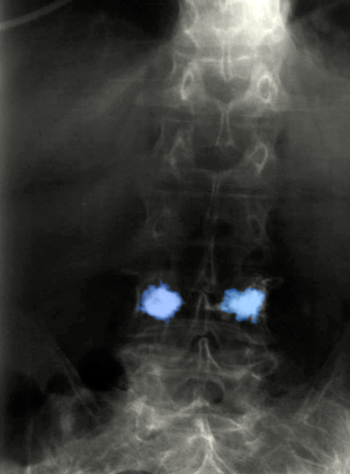

Σπονδυλοπλαστική οσφυϊκού σπονδύλου. |